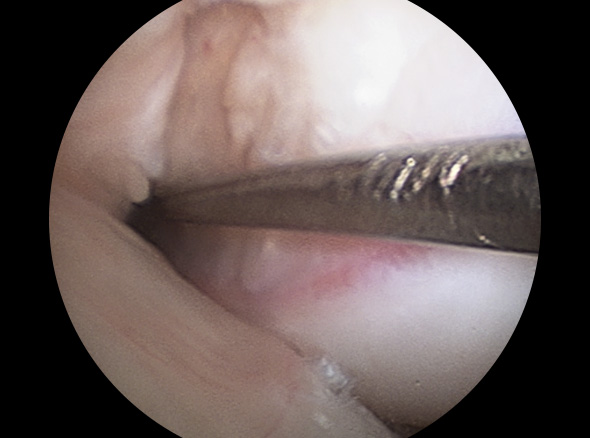

이식할 인대 삽입